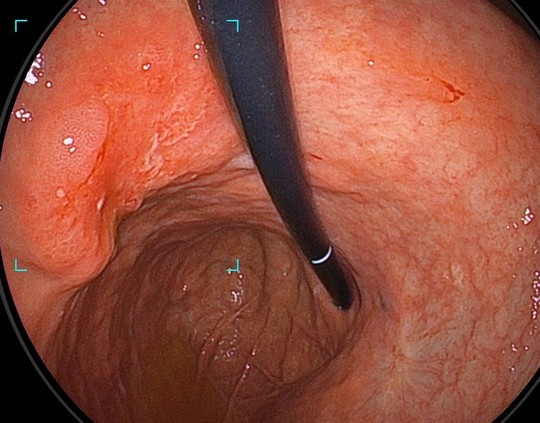

大腸カメラ

大腸ポリープ/大腸がん/腸の炎症などを調べる検査です。便潜血の精密検査や内視鏡ドックも行っています。つらくない大腸カメラ(内視鏡)を行っています。

内視鏡治療

豊富な経験による内視鏡治療と日帰りポリープ切除も行っています。当院では、内視鏡検査で見つかった病変について検査と同時に治療も行っています。正確な診断技術があるからこそ可能な治療です。

大腸内視鏡

大腸内視鏡は病変の発見と診断そしてその病変の治療に高度な技術が必要です。

技術によって検査と治療の質が大きく変わるのが内視鏡検査です。

当院では国立がんセンター中央病院で行ってきた豊富な技術を活かして確実に診断と治療を行います。

大腸カメラ(下部消化管内視鏡検査)

AIと専門医の目で瞬時にポリープを発見